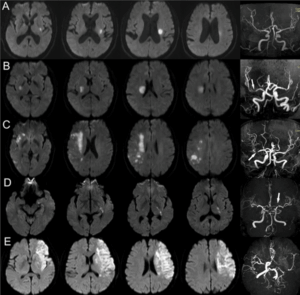

全天候24小時緊急磁力共振造影MRI檢查,快速診斷急性中風

- 緊急磁力共振MRI造影對於在中風黃金小時內進行準確診斷至關重要,尤其是對於缺血性中風。

- MRI 可提供腦部及其血管的詳細影像,從而評估中風類型。

- MRI 亦可顯示缺血性中風時血管阻塞的部位和範圍,或出血性中風時出血的部位和範圍,從而提供選擇合適治療方案的指導。

全天候24小時 (24/7) 緊急磁力共振MRI造影,快速診斷急性中風

- 在香港腦脊中風及痛症狀顧問中心,我們提供全天候24小時 (24/7) 緊急磁力共振MRI造影服務,可在中風症狀出現時提供快速準確的診斷。

- 及時進行 MRI 中風診斷,以便在黃金小時內及時有效治療,拯救大腦,減少長期殘疾並改善復康效果。